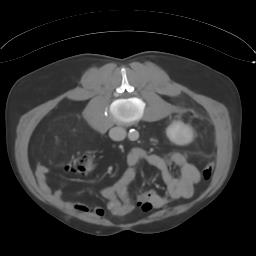

Sparse-view computed tomography (CT) -- using a small number of projections for tomographic reconstruction -- enables much lower radiation dose to patients and accelerated data acquisition. The reconstructed images, however, suffer from strong artifacts, greatly limiting their diagnostic value. Current trends for sparse-view CT turn to the raw data for better information recovery. The resultant dual-domain methods, nonetheless, suffer from secondary artifacts, especially in ultra-sparse view scenarios, and their generalization to other scanners/protocols is greatly limited. A crucial question arises: have the image post-processing methods reached the limit? Our answer is not yet. In this paper, we stick to image post-processing methods due to great flexibility and propose global representation (GloRe) distillation framework for sparse-view CT, termed GloReDi. First, we propose to learn GloRe with Fourier convolution, so each element in GloRe has an image-wide receptive field. Second, unlike methods that only use the full-view images for supervision, we propose to distill GloRe from intermediate-view reconstructed images that are readily available but not explored in previous literature. The success of GloRe distillation is attributed to two key components: representation directional distillation to align the GloRe directions, and band-pass-specific contrastive distillation to gain clinically important details. Extensive experiments demonstrate the superiority of the proposed GloReDi over the state-of-the-art methods, including dual-domain ones. The source code is available at https://github.com/longzilicart/GloReDi.